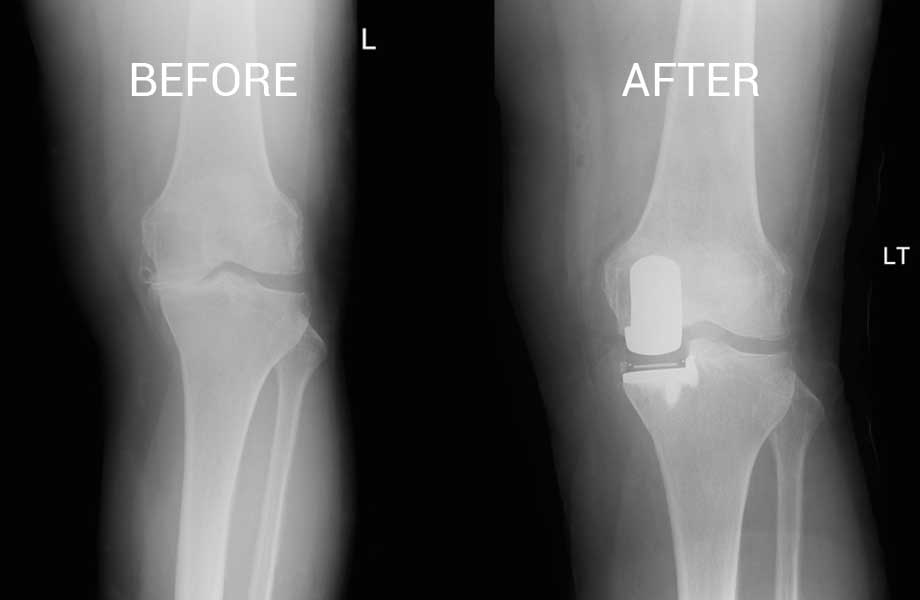

Total Knee Replacement